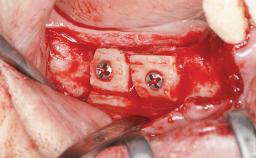

Bone Augmentation Horizontal|Simultaneous|Sinus Floor Elevation|Staged

Bone Volume Deficient vertically or deficient vertically AND horizontally